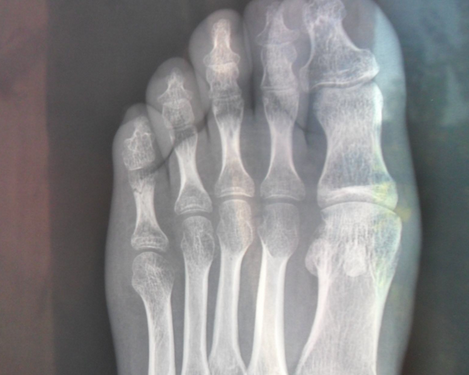

裂纹骨折的诊断在普通X片上常会漏诊,裂纹在没有明显移位时常看不见,这就需要CT和核磁共振(MRI)来进一步明确诊断,MRI可根据组织在磁场中的信号强度变化来显示包括骨水肿在内的病变。